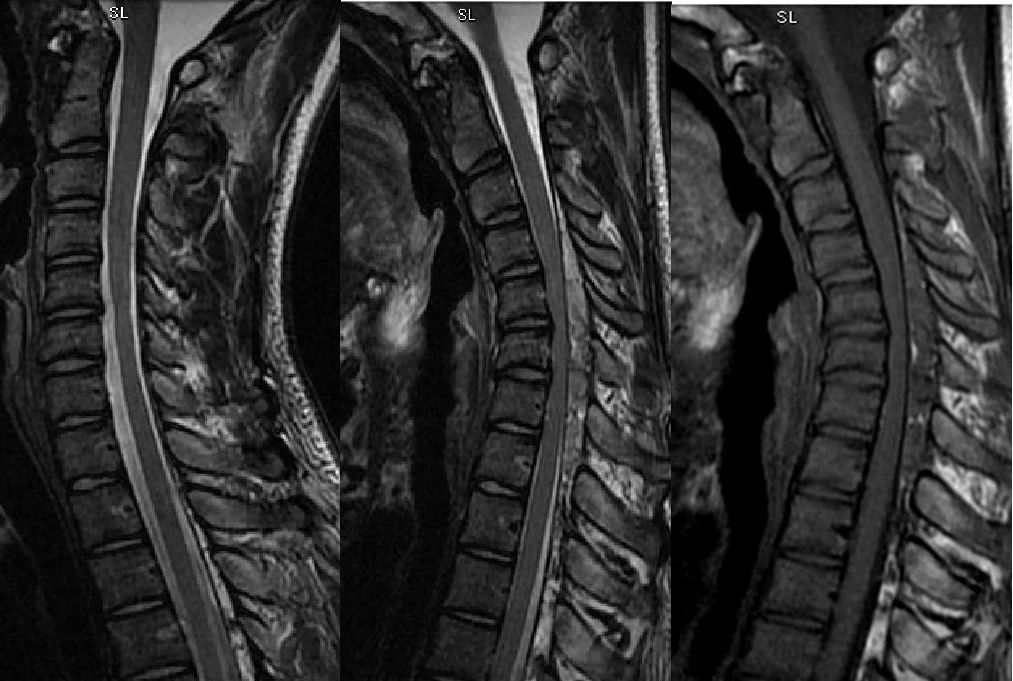

T2 T2 T1

T1 T1+C